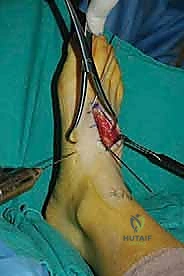

Lateral Incision (Lateral Second and Third TMT Joints):

- "Next, let's make our second incision. This is another 4-cm longitudinal incision, centered directly over the third TMT joint."

- "Again, deepen carefully through the subcutaneous tissue, being mindful of the dorsal cutaneous nerves. These are even more prevalent laterally. Blunt dissection is your friend here."

- "You'll encounter the extensor digitorum brevis (EDB) muscle belly. Typically, we cannot simply retract the EDB plantar without causing undue tension on the neurovascular structures or the muscle itself. Therefore, we will split the EDB longitudinally, directly in line with our skin incision. This provides excellent exposure without excessive soft tissue trauma."

- "Once the EDB is split, identify the capsule of the third TMT joint. Again, split the periosteum and capsule in line with the joint to avoid excessive stripping."

- "Through this incision, we can also expose the lateral aspect of the second TMT joint and the space between the second and third metatarsal bases."